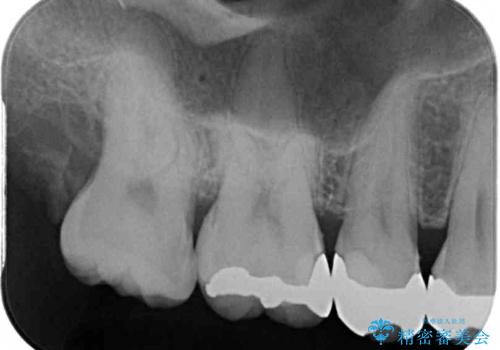

左上の奥歯は神経が失活しており、根管治療が必要な状態でした。

その他は銀歯のインレー(部分的な詰め物)が装着されており、それらはむし歯を除去した後にセラミックインレーにて修復治療を行い、左下と根管治療を行う左上の奥歯はオールセラミッククラウンにて補綴治療を行うこととしました。